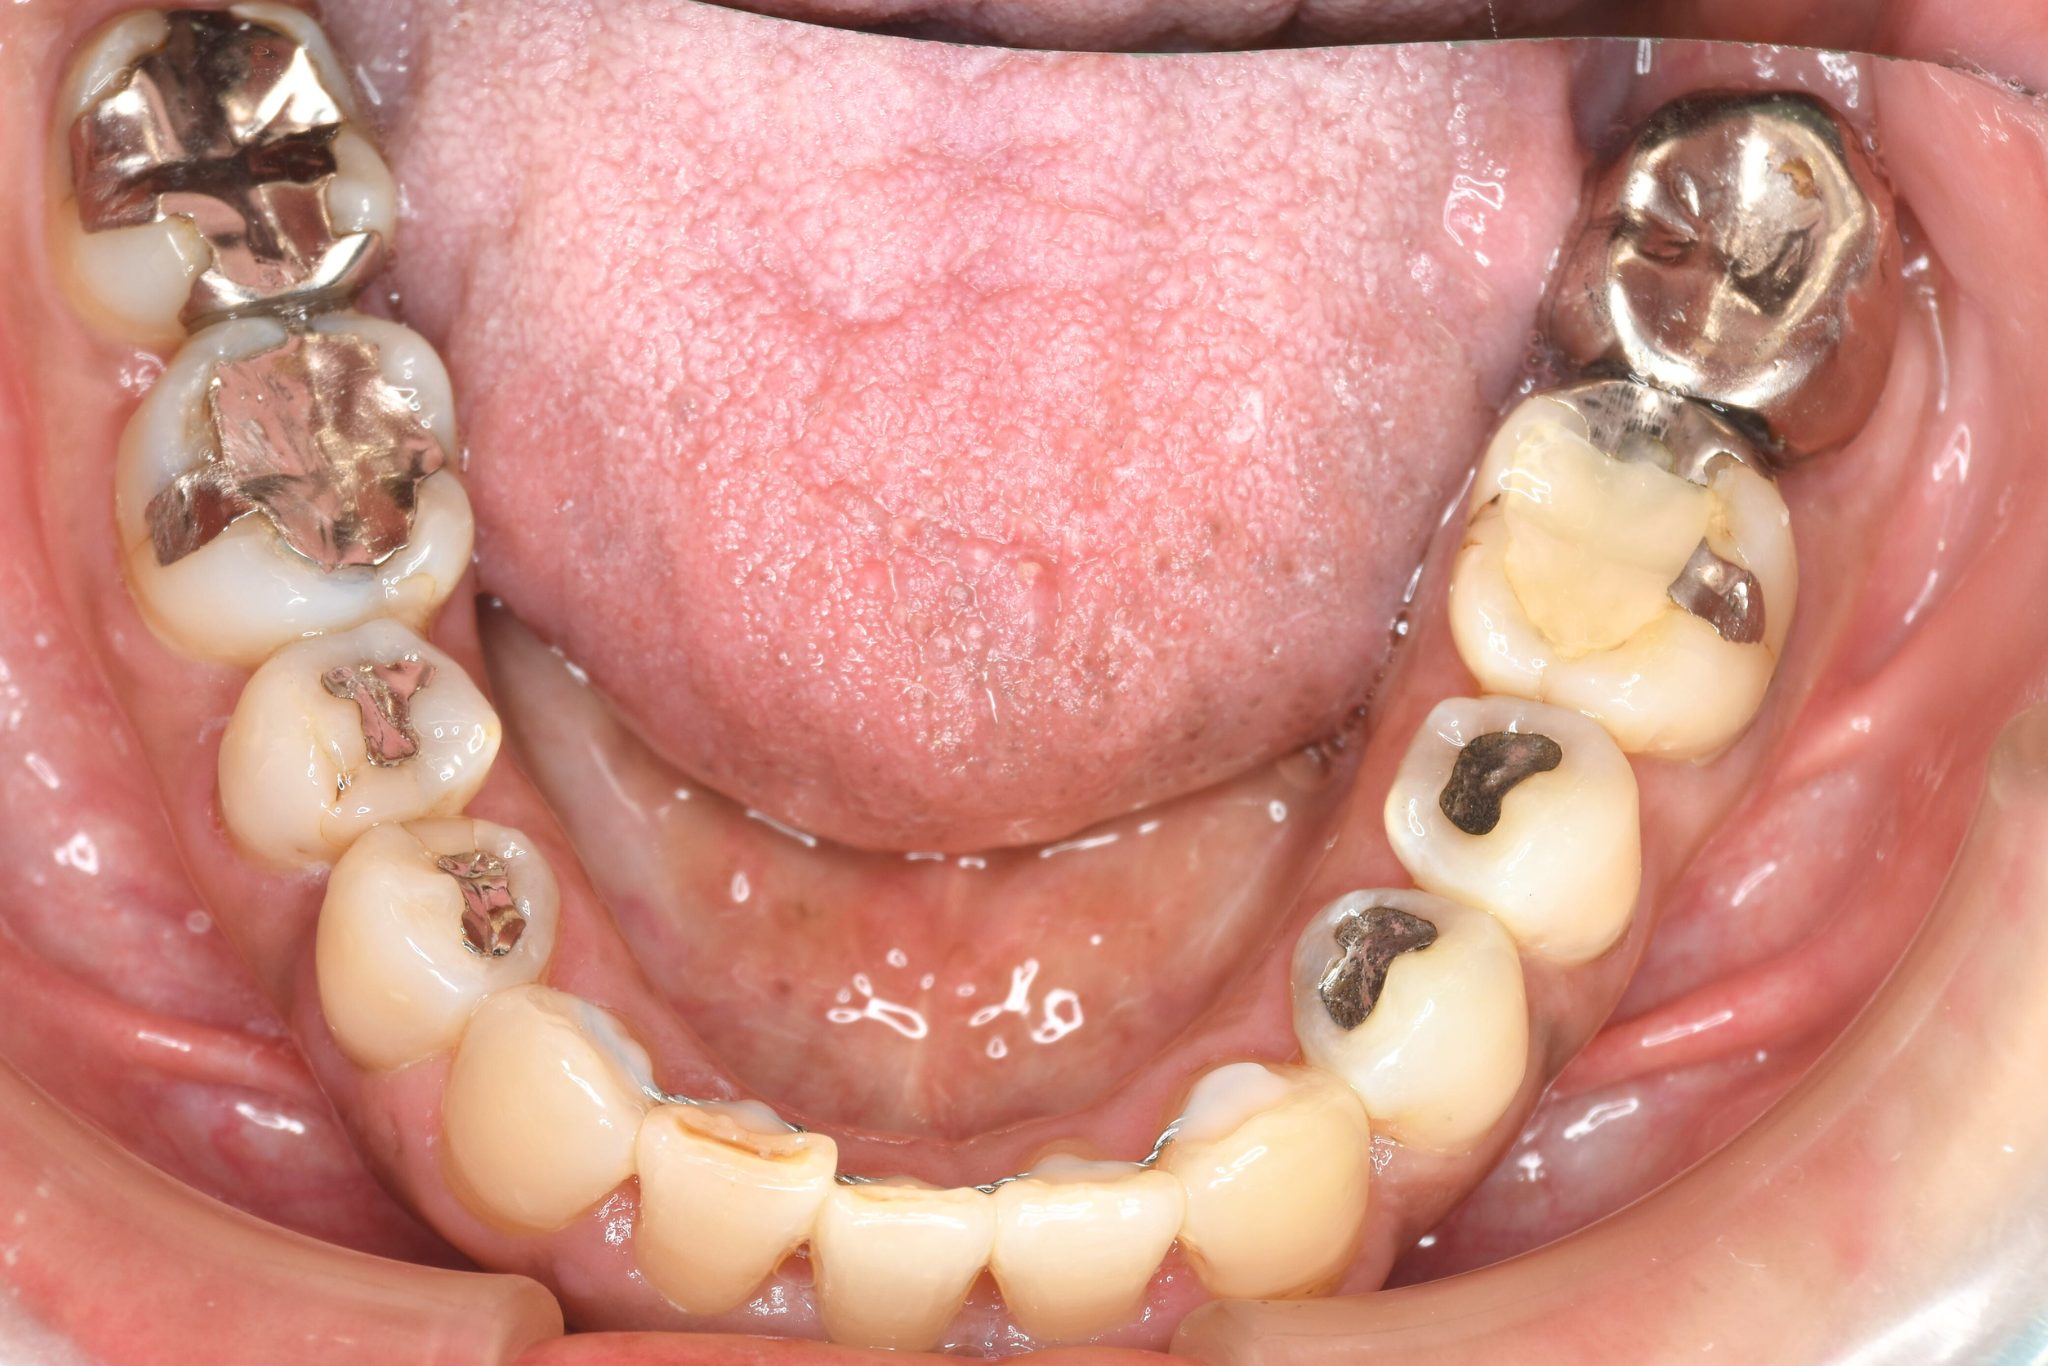

ビフォー

ワイヤー矯正治療|症例_588

主訴 かみ合わせ ※抜歯あり

施術内容 MSEと下顎リンガルアーチを用いて上下顎骨を拡大した。

その後下顎前歯を1本抜歯してマルチブラケット装置を用いて

歯牙を配列し良好な咬合を獲得した。側貌は改善した。